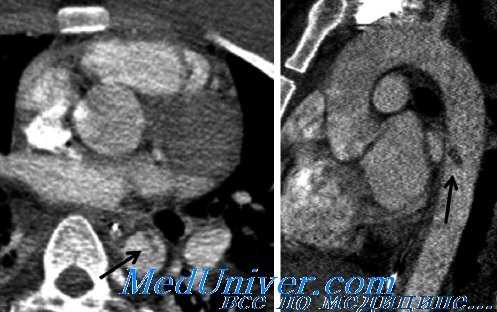

примеры разрыва аорты – восходящей (a) и брюшной (b), при которых операция может быть эффективна